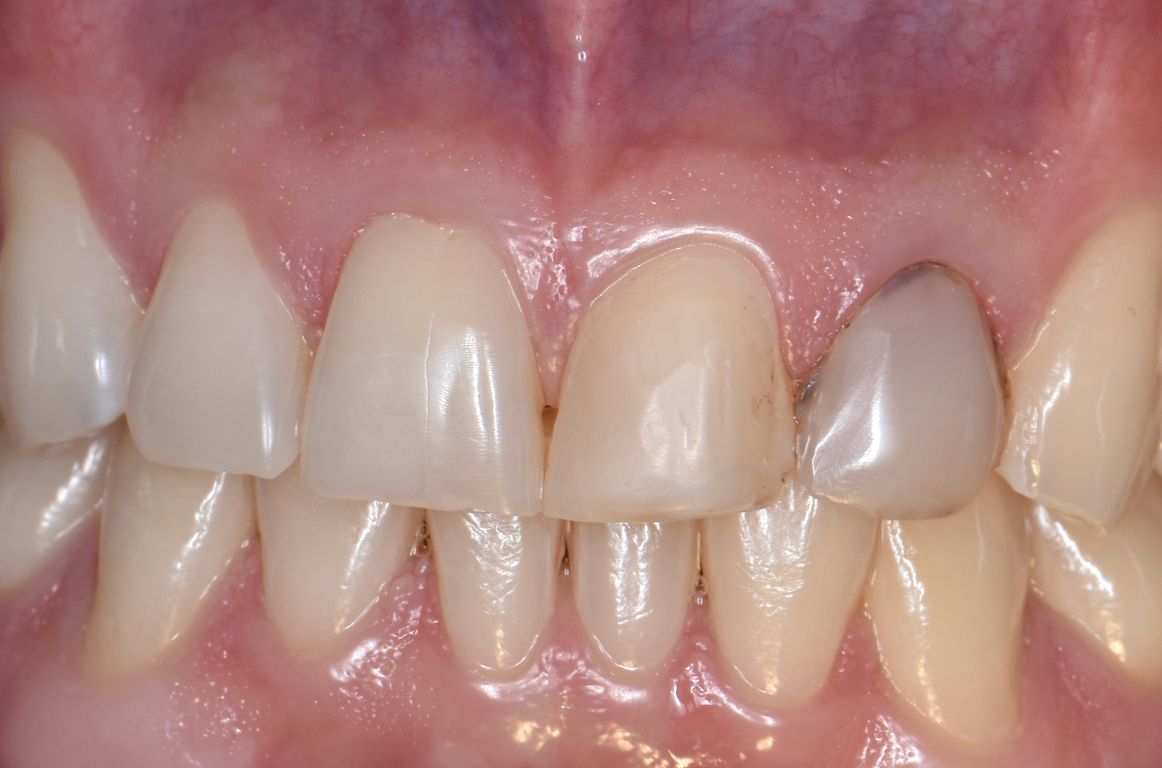

Los frenillos labiales o lineales son tejidos conectivos (muscular y fibroso) que unen la cara interna del labio (labial) y la base de la lengua (lingual) con la encía. En el caso del frenillo labial puede generar diademas (separación entre los dientes centrales), fenestraciones (desplazamiento de encía en los incisivos inferiores exponiendo las raíces), es por esto que se realiza la cirugía para eliminarlo y así se logran unir con ortodoncia. En el caso del frenillo lingual puede generar problemas de pronunciación (problemas con la R, L), y al eliminarlo la corrección de este problema es inmediata. La recuperación es de 3 a 5 días, y se indican analgésicos/antiinflamatorios.